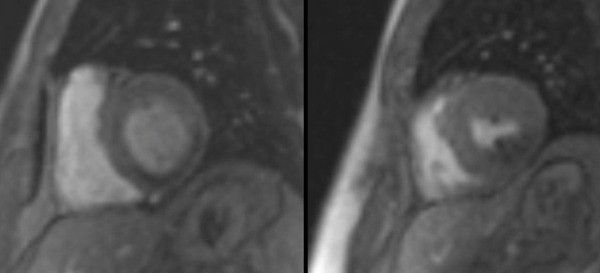

Stress Perfusion CMR